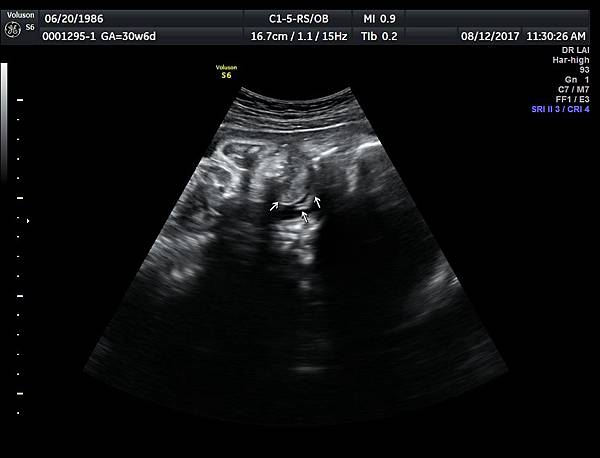

2017年8月12日一位22歲第二胎的孕婦在診所接受胎兒高層次及心臟超音波檢查,她說因為第一胎沒有兔唇但是顎裂,上網搜尋相關資訊所以來到診所安排檢查:她知道我會看懸雍垂(因為懸雍垂是軟顎最後形成的位置,如果看到完整懸雍垂,可以間接診斷正常的顎)

一個檢查如果要花很長的時間才能完成,這樣的檢查無法變成常規的篩檢方式,我已經在我的診所執行懸雍垂檢查一段時間,我檢查懸雍垂大約30 秒,前提是胎兒的臉最佳位置是側躺,其次是側躺偏向上,我的檢查步驟是上顎(含日後大門牙長出的位置)、舌頭、懸雍垂(= equal sign)(附圖1~8),如果超過60秒無法完成,只有兩個原因,一個是胎兒姿勢不適合或喉嚨羊水空間太小,這時候不要硬碰硬,只要先檢查其他部位,等待時機再回來即可,我的經驗是90%的cases都能順利完成這項檢查(肚皮厚的case真的是很難)。